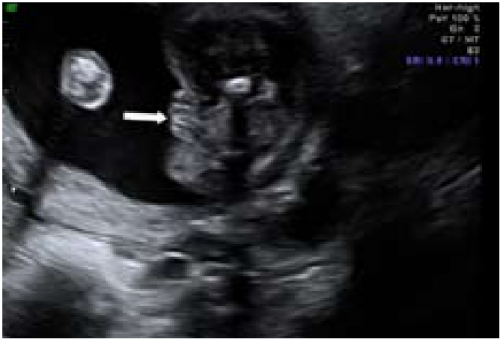

sagittal sign שתואר לראשונה על ידי Emerson וחב'[4] הוא הסמן הסונוגרפי המקובל ביותר לקביעת מין העובר בשלבי ההיריון המוקדמים. העובר נסרק בחתכים סגיטליים בקו האמצע. באזור העכוז הנסרק בחתך זה, ניתן לזהות בליטה שמייצגת את הדגדגן או את איבר המין הזכרי. כאשר כיוון הבליטה כלפי מעלה, מין העובר זכר (תמונה 1) וכיוון כלפי מטה מבטא מין נקבה (תמונה 2). שימוש בסמן סונוגרפי זה אפשר לזהות מין העובר ב-71 אחוז (5\7) מהעוברים בשבוע 10 עד 11.9, אך האבחנה היתה נכונה ב-60 אחוז (3\5) בלבד. דיוק האבחנה עלה עם התקדמות גיל ההיריון ל-75 אחוז, 100 אחוז, 98 אחוז ו-100 אחוז בשבועות 12-13.9, 14-15.9, 16-17.0 ו-18-20.4, בהתאמה[4]. דיווחים רבים אחרים דיווחו על אבחון מין העובר בסוף הטרימסטר הראשון ותחילת השני (14-4) (ראו טבלה 1).

ברונשטיין וחב׳[7] דיווחו שדיוק אבחון מין העובר על ידי אולטרסאונד נרתיקי עולה עם הניסיון, כך שבשנתיים הראשונות לשימוש באולטרסאונד נרתיקי, המין אובחן בדיוק של 76 אחוז ועלה ל-80 אחוז בשנתיים לאחר מכן בין השבועות 14-13 להיריון, ובשבוע 16-15 הדיוק עלה מ-88 אחוז בשנתיים הראשונות לנסיונם ל-96.7 אחוז בשנתיים לאחר מכן. בעבודה זו, מין זכר נקבע על סמך הדגמת מבנה דמוי כיפה (dome sign) המייצג שק אשכים (תמונה 3) בעוד מין נקבה נקבע על סמך הדגמת שניים או ארבעה קווים מקבילים (parallel lines) המייצגים את השפתיים הקטנות והגדולות (תמונה 4) . סימנים סונוגרפיים נוספים בעבודה זו[7] היו הדגמת קו אקוגיני הנמשך מבסיס ועד קצה איבר המין הזכרי ומייצג קו האמצע של הפניס (תמונה 5) וכיוון הפאלוס העוברי (כלפי מעלה מייצג זכר וכלפי מטה נקבה).